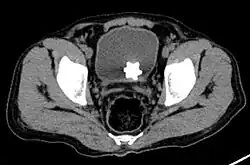

A star-shaped Jackstone urolith can be seen in the urinary bladder on this radiograph of the pelvis

Jackstone calculi are rare bladder stones that have an appearance resembling toy jacks. They are almost always composed of calcium oxalate dihydrate and consist of a dense central core and radiating spicules. They are typically light brown with dark patches and are usually formed in the urinary bladder and rarely in the upper urinary tract. Their appearance on plain radiographs and computed tomography in human patients is usually easily recognizable. Jackstones often must be removed via cystolithotomy.[10]